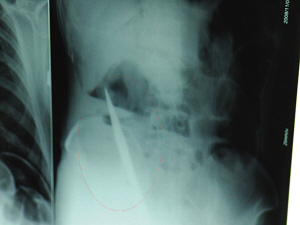

X光片上,尖刀清晰可見。

從男子體內(nèi)取出的尖刀足足有19厘米長。

6日上午,記者在徐州礦務(wù)集團(tuán)總醫(yī)院重癥監(jiān)護(hù)室見到了這名男子,目前他雖然已經(jīng)恢復(fù)了意識,但還不能開口說話,需要呼吸機(jī)輔助呼吸。據(jù)醫(yī)生介紹,4日中午12時(shí)左右,這名男子因服毒輕生被緊急送到醫(yī)院進(jìn)行搶救,之前,這名男子已經(jīng)在當(dāng)?shù)剜l(xiāng)鎮(zhèn)醫(yī)院進(jìn)行了近20小時(shí)的治療,但效果不佳。“病人被轉(zhuǎn)院到礦總院時(shí)已神志不清,血壓極低,處于休克狀態(tài)。”救護(hù)人員給男子洗胃、初步處理以后,發(fā)現(xiàn)男子呼吸急促,于是趕緊給他拍片檢查。結(jié)果讓所有的醫(yī)生大吃一驚,竟有一把尖狀異物橫在該男子腹腔內(nèi)!當(dāng)天下午5時(shí)30分,輕生男子被推上了手術(shù)臺。經(jīng)過40多分鐘的手術(shù),該男子腹腔被打開,手術(shù)醫(yī)生發(fā)現(xiàn),男子體內(nèi)的金屬狀異物竟然是一把長19厘米的尖刀!